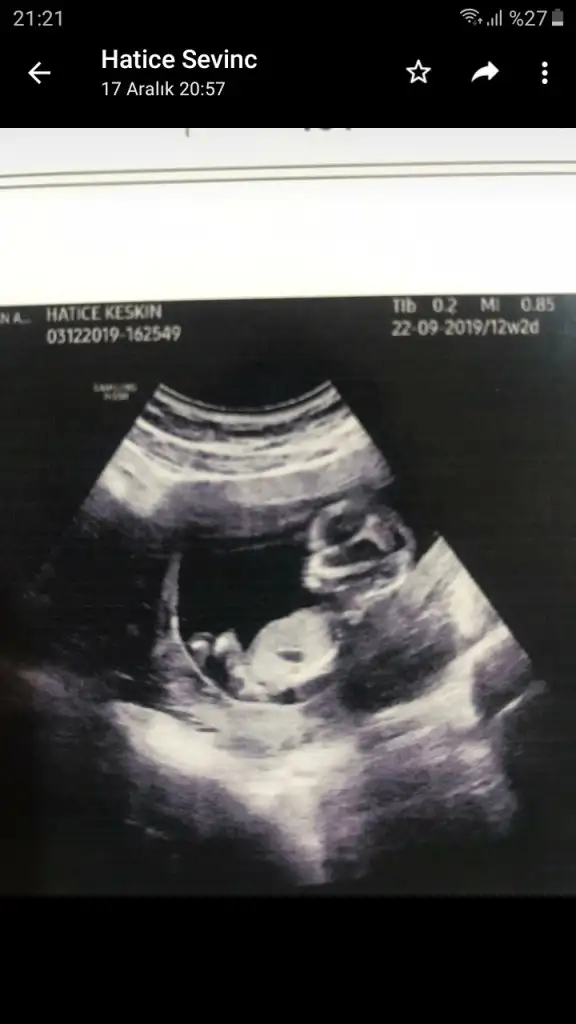

dr soylemeden siz gorun genital nub teorisi ( bebegin cinsiyeti)

Siz de yine bakarmısınız net söyledi kız diye herkes erkek demişti sizin gibi bende öyle diyordum ama ters köşe yaptı galiba bizimki çok hareketliydi 🤭🤣

ya kızlar bu resim bnim kaç gündür aklımı karstryo burda kız gibi doktor erkek dedi